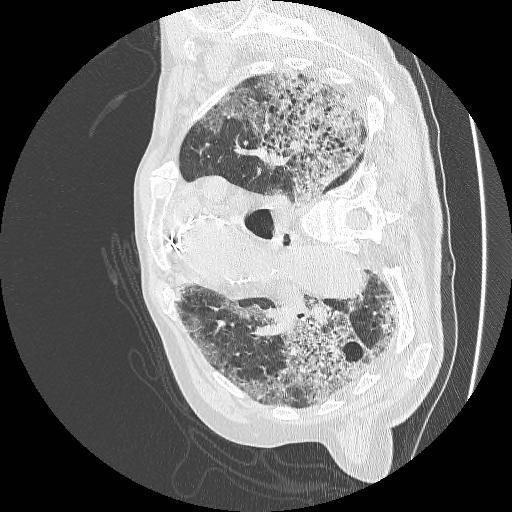

The following is an AI medical segmentation tool for detecting ground-glass, consolidation and pleural effusion in patient lung CT scans. Some reports have shown that ground-glass/consolidation measurements can further enhance the prognosis estimation for Covid-19 patients.